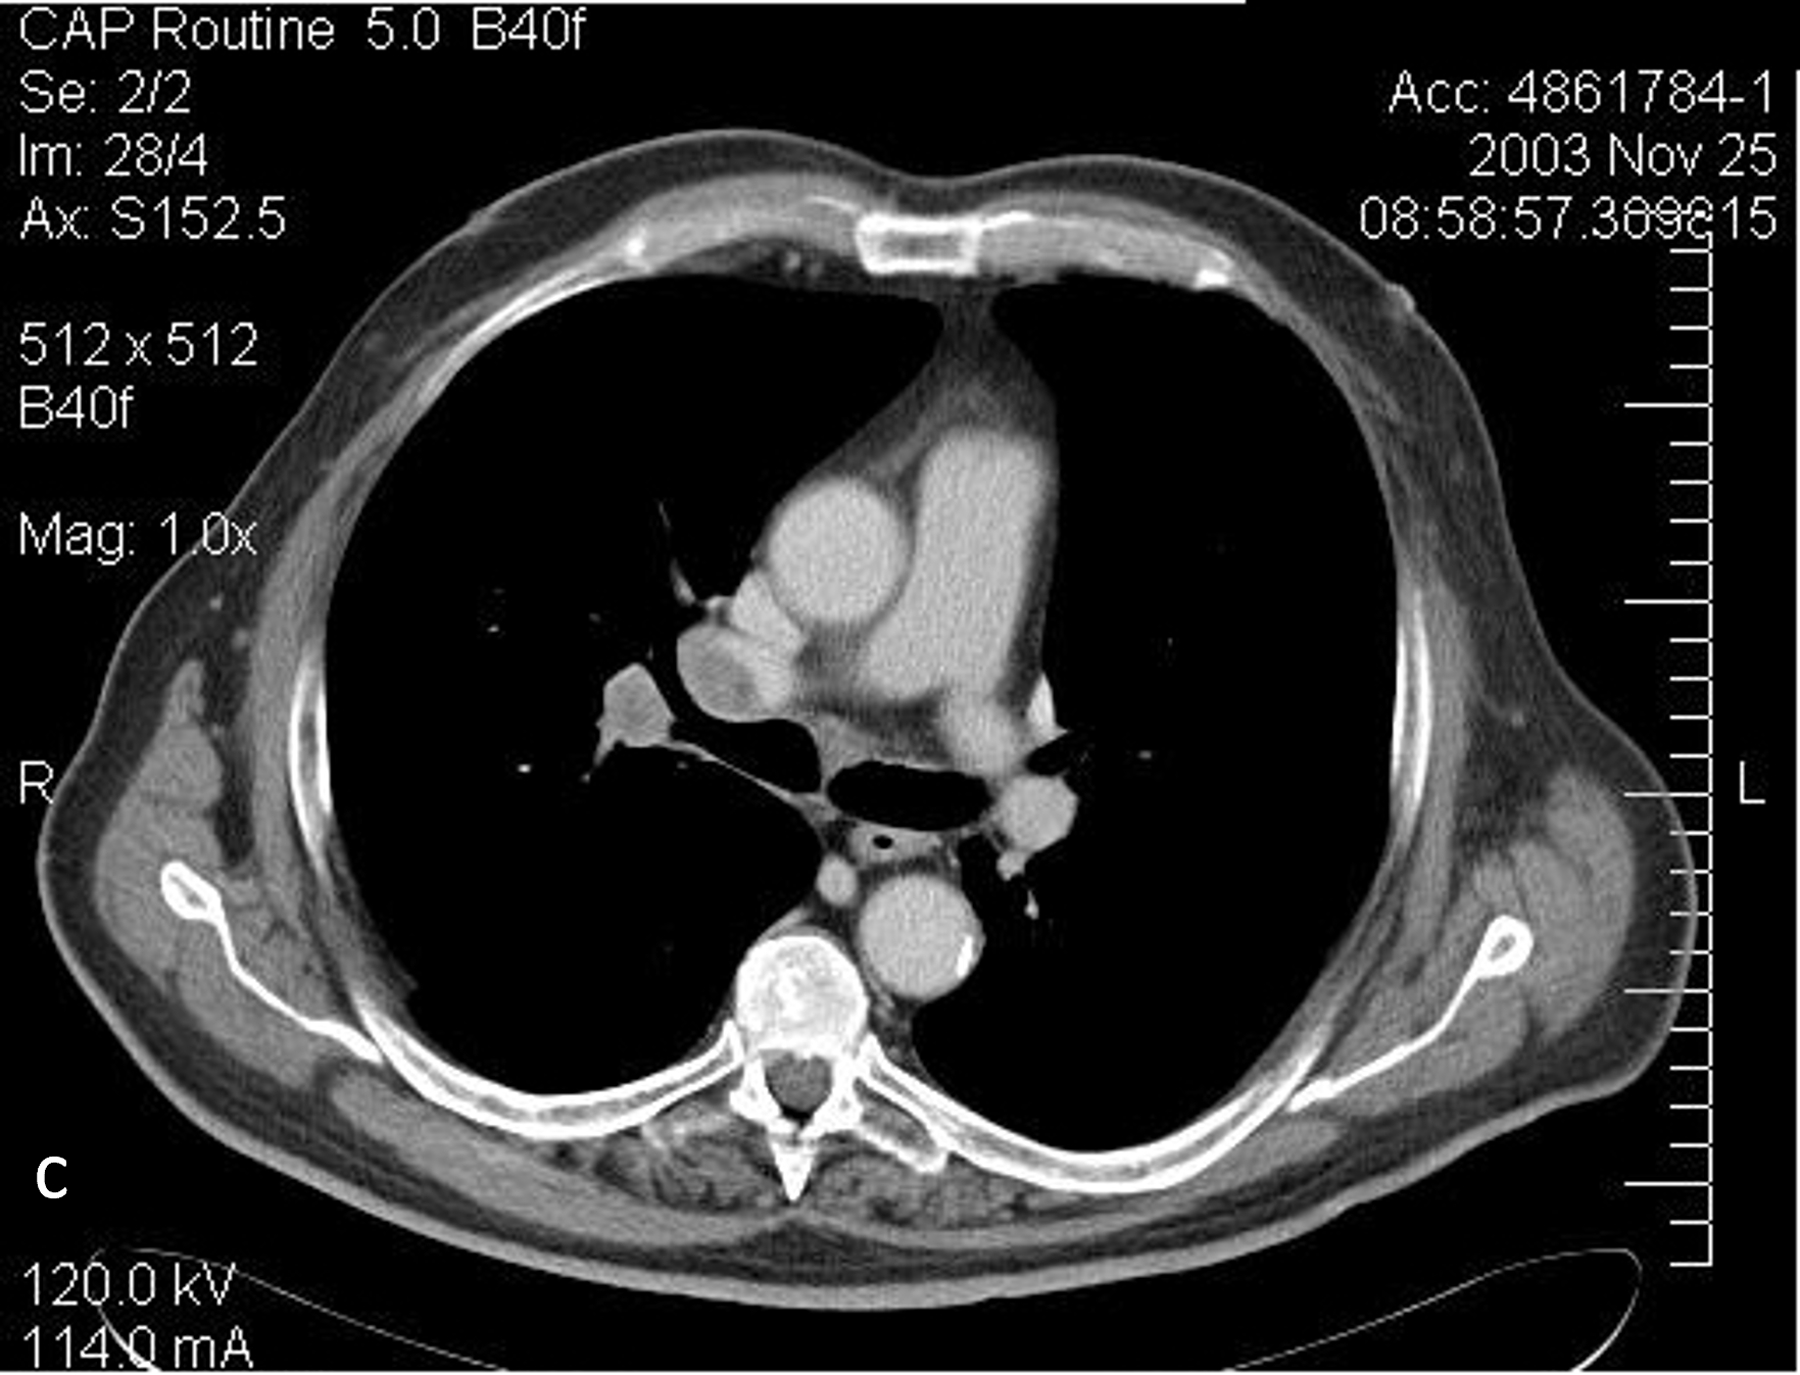

Figure 8.

Illustration of angular and longitudinal tube current modulation, which varies the tube current according to the patient thickness (a). Scanned projection radiograph (b) and axial CT images at the levels of the upper thorax (c, 95 mAs), middle thorax (d, 101 mAs), liver (e, 369 mAs), and pelvis (f, 205 mAs) demonstrating the change in tube current associated with the change in body habitus. Reprinted, with permission, from reference (48).